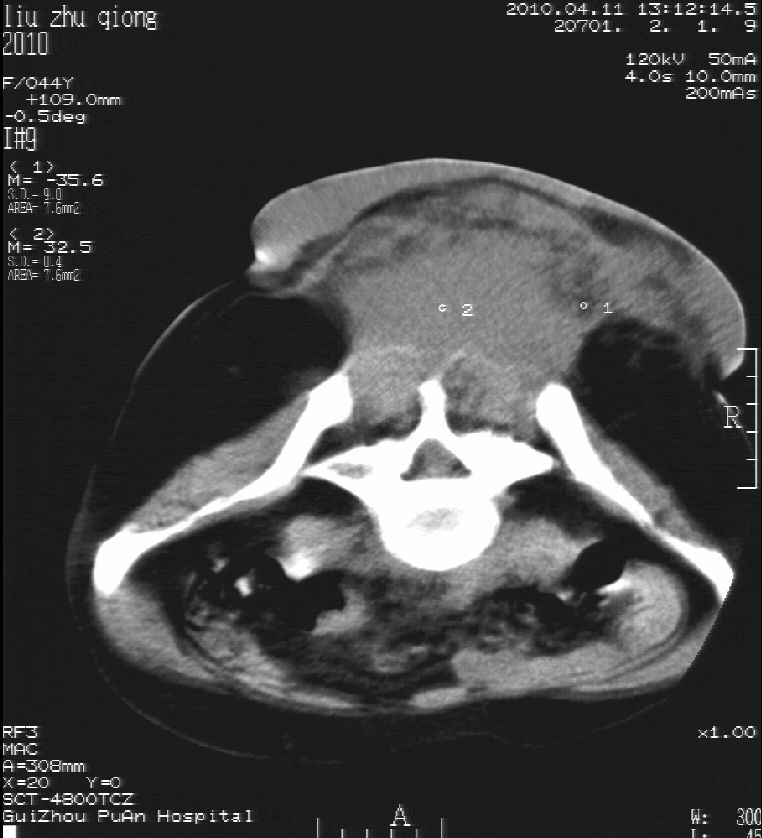

刘某,女,44岁,生第一胎时发现腰背部肿块,黄豆大小,至今17年,呈逐年增大,现行ct检查如下,敬请各位指点。

病史:女,44岁,腰背部肿块,黄豆大小,17年,呈逐年增大。

ct示:骶骨见软组织密度影,似见细条状,或花边状高密度影,考虑不典型钙化灶,向后生长,超出皮肤,可见骶骨破坏,第5幅ct图似与骶管相通。

病程长,生长慢,肿块巨大,考虑神经纤维瘤,脂肪密度可以用肿瘤生长过程中包裹入皮下脂肪解释。